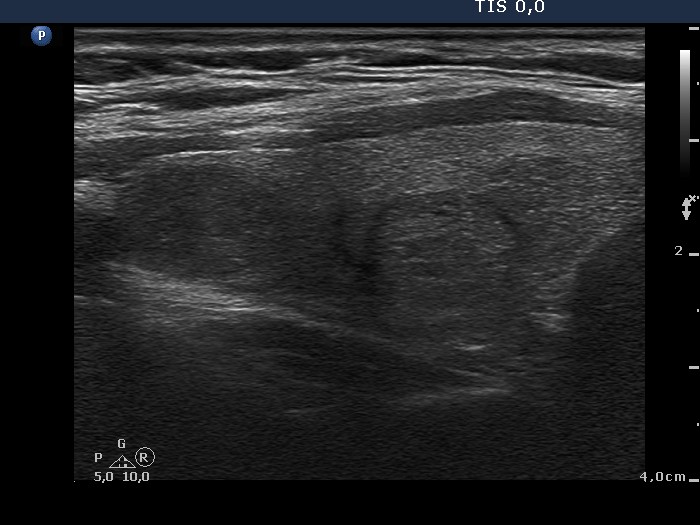

Ultrasound. The thyroid was echonormal. There were two lesions in the right lobe, the upper one was minimally hypoechogenic and had blurred borders while the nodule in the middle part of the lobe was inhomogeneous and displayed halo. Both nodules presented perinodular blood flow. The upper lesion was not noticed in the previous examination 4 years ago.

Aspiration cytology was performed from the nodule in the upper part of the right lobe. Our cytological report was suspicion of papillary carcinoma with around 10% risk of malignancy.

The lesion in question was not present four years earlier and had blurred borders. Both of these circumstances increased the likelihood of malignancy.